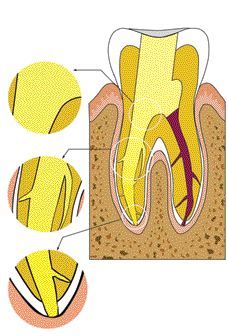

Change is a significant evolutionary tool provided it rests upon a solid and secure foundation. Innovations in materials and technologies occurring within the dental field are impacting powerfully on its art and science; however, dentistry, like all health care, is both a business and a profession. The pendulum swings that predicate trends and transitions within … Read more